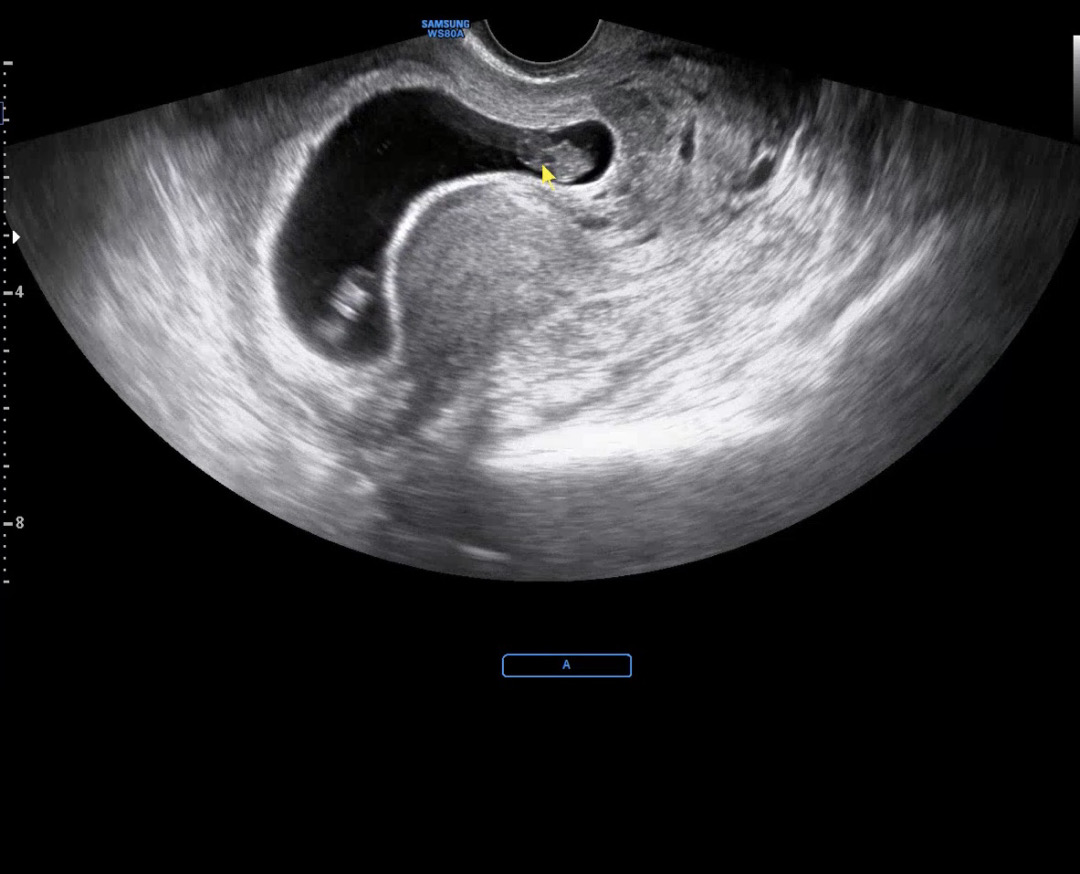

저는 첨에 아기집 볼때만 해도 쌍둥이 인줄 모르다가 ㅎㅎ다른날 병원에 갔더니 일란성 쌍둥이라네요,, ㅎㅎ 아짓 증말 쪼꼬미라 벌써 무섭네요… 배가 얼마나 나올지 ….

어머나~ 양쪽끝에 하나씩 잘 자리 잡앗네요 ㅎㅎ 귀여워라 🥹 쌍둥이면 입덧두 심하실텐데 아가들 생각하시면서 힘내세요!! 화이팅입니당 ♥️

우아 쌍둥이 아기집이라 그런가 뭔가 넓어보이긴 하네요 !! 신기해용 ㅎㅎ